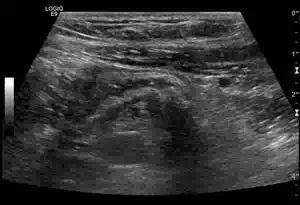

Längsschnitt über der Gallenblase

Die Gallenblase ist deutlich wandverdickt und mehrschichtig. Die echoarmen (im Bild dunklen) Wandanteile sind Flüssigkeitseinlagerungen im Rahmen der akuten Cholezystitis